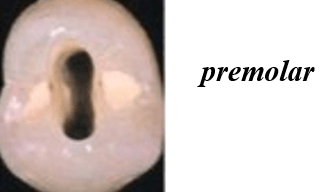

Shapes of the access cavity of all teeth

| Tooth | Access cavity shape | Average depth |

|---|---|---|

| Maxillary incisors | Triangular or oval (placed over the palatal surface) |

3-4 mm |

| Mandibular incisors | Triangular (placed over the lingual surface)

|

3-4 mm |

| Maxillary canines | Oval (placed over the palatal surface)

|

4-5 mm |

| Mandibular canines | Oval (placed over the lingual surface)

|

4-5 mm |

| Maxillary premolars | Oval or rounded (located over central part of the tooth)

|

4-5 mm |

| Mandibular premolars | Oval (over central of the tooth, slightly to the lingual)

|

4-5 mm |

| Maxillary molars | Trapezoidal (located over the mesial buccal cusp or the central part of the tooth)

|

5-6 mm |

| Mandibular molars | Trapezoidal or rhomboidal (centered over the mesial buccal cusp)

|

5-6 mm |

| Maxillary second molars | Trapezoidal (centered more mesially and palatally, slightly off-center) | 5-6 mm |

| Mandibular second molars | Trapezoidal or rhomboidal (centered over the mesial buccal cusp) | 5-6 mm |

| Maxillary third molars | Oval or trapezoidal | 5-7 mm |

| Mandibular third molars | Trapezoidal | 5-7 mm |